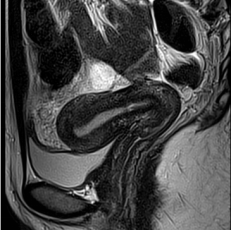

2. 图像质量影响(最常见):这是更实际的问题。节育器中的金属(即使是铜等非铁磁性金属)会在MRI图像上产生金属伪影,表现为图像局部扭曲、变形或出现大片黑影。如果检查部位正好是盆腔、子宫或附件,这些伪影会严重干扰医生观察病灶,可能导致“白做一次检查”,既耽误时间又影响诊断。

图1 部分子宫节育器在MRI上的伪影对结构无法评估